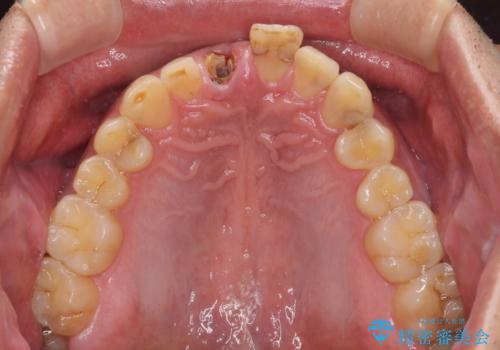

- 前歯の被せものが脱離したとのことで来院された患者様です。

診察の結果、前歯が縦に破折しており、抜歯が必要と診断されました。